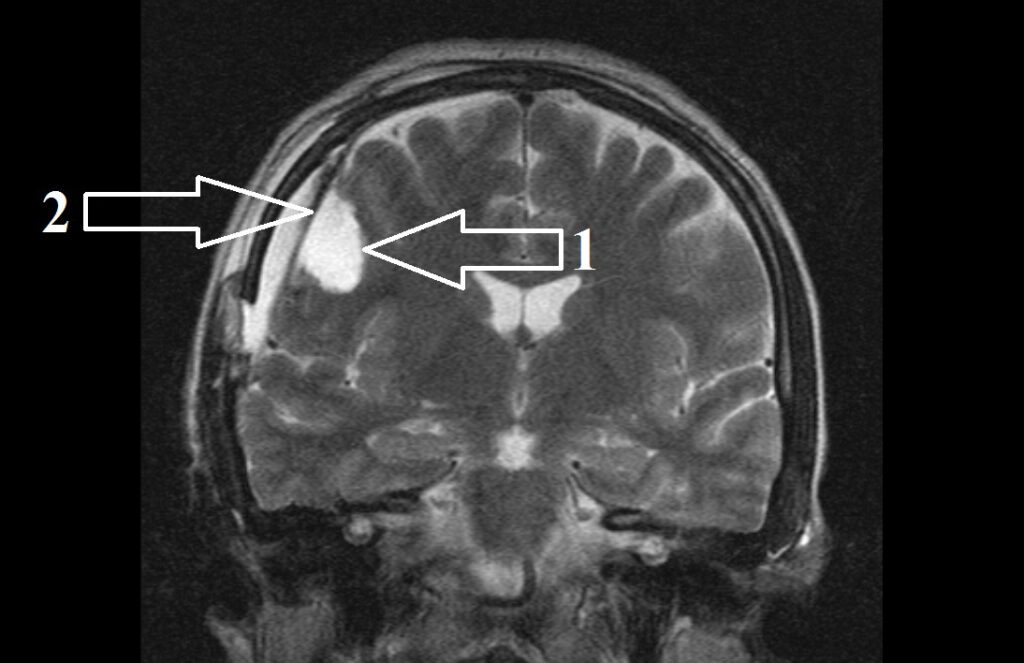

Медицинские аспекты и диагностика субдуральной гигромы мозга